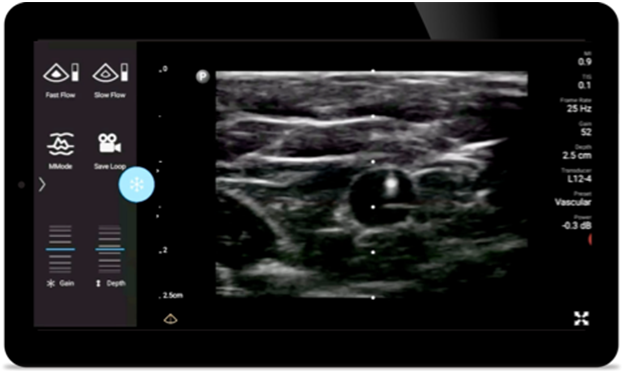

Reduce complications in needle guided procedures

Lumify handheld ultrasound for anesthesiology helps you clearly visualize border definition with your needle placement, surrounding nerves, vessels and fascial planes.

Lumify transducers for anesthesiology

Lumify L12-4 broadband linear array transducer